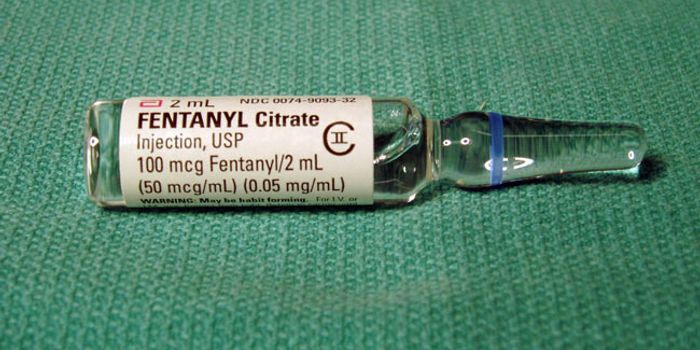

FEB 23, 2016Health & MedicineOpioid addiction is a huge problem, with about 2 million Americans suffering from addiction to prescription pain relieve ...